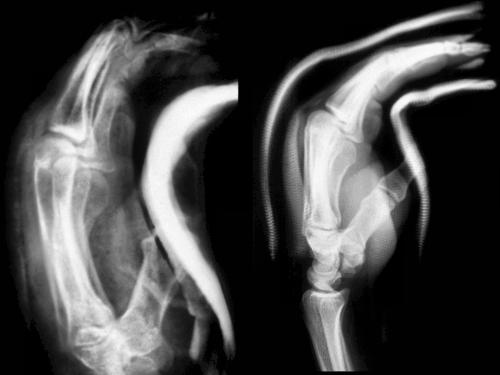

Safe hand position is sometimes difficult to maintain with splinting.

The thickly padded palmar plaster splint applied in the emergency room

is usually totally inadequate (left), but even a cast which appears

correct may not be if the palmar flexion point is constructed distal to

the center of the palm (right).